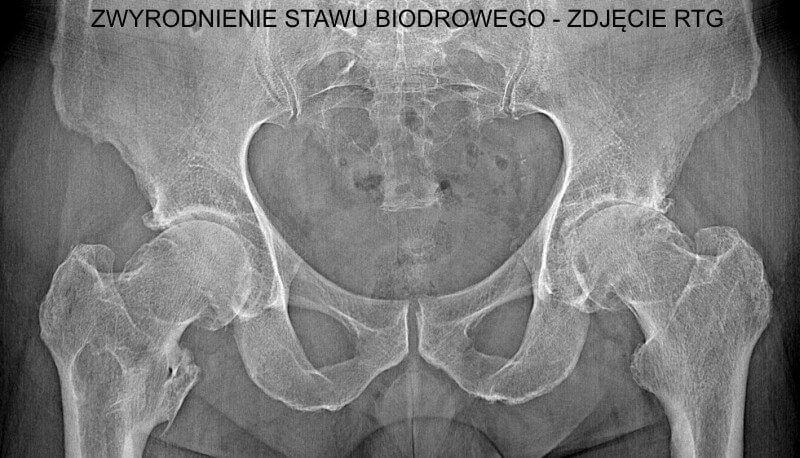

Diagnosis of Osteoarthritis of the Hip

The diagnosis of hip osteoarthritis begins with a detailed medical history and physical examination by a doctor, who will consider current symptoms, medical history, and previous injuries the patient may have experienced. However, additional imaging tests are required to confirm the diagnosis and assess the severity of the condition.

- X-ray – Allows the evaluation of cartilage condition, joint space narrowing, and the presence of osteophytes (bone spurs).